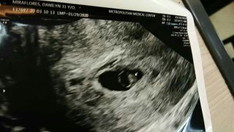

Papano kasi. Pg gising ko nkita ko may spotting di ko alm ggawin ko akala ko nagkaperiod n ko ulit!sobrang natense ako hndi para sa sarili ko kundi dahil sa baby s tyan ko. Ginawa ko nag pt ulit.. Malabo.. Naghanap ako clinic, hospital.. Para malaman kung ano ba to.. Nagpacheck up tuloy ako ng di oras.. Kung ano2 test pinagawa ko.. Kahit napagastos ako ok lng basta malaman ko lang kung ano nanyari s knya.. So far nmn awa ni lord ok sya.. Nag spotting pl tlg pg 1st trimester wag lng daw bleeding.. Sched ng trans v ko saturday pa pero napa aga na.. Hehe gsto n nya mkita sya ng mama nya.. Gsto nya n ipakita sakin n may heartbeat na sya ?? ang saya sa pakiramdam mga mommy. 6 weeks n pla sya #Kabado #MomFeelsLike